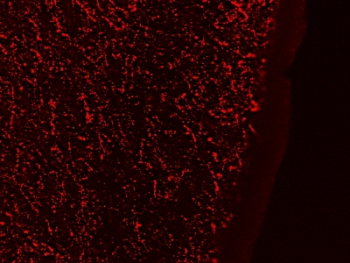

IHC staining of a PFA-perfused cryosection of human hypothalamus with Galanin antibody at 0.3ug/ml. HIER: pH6 citrate buffer at 80oC for 30min, Cy3-staining.